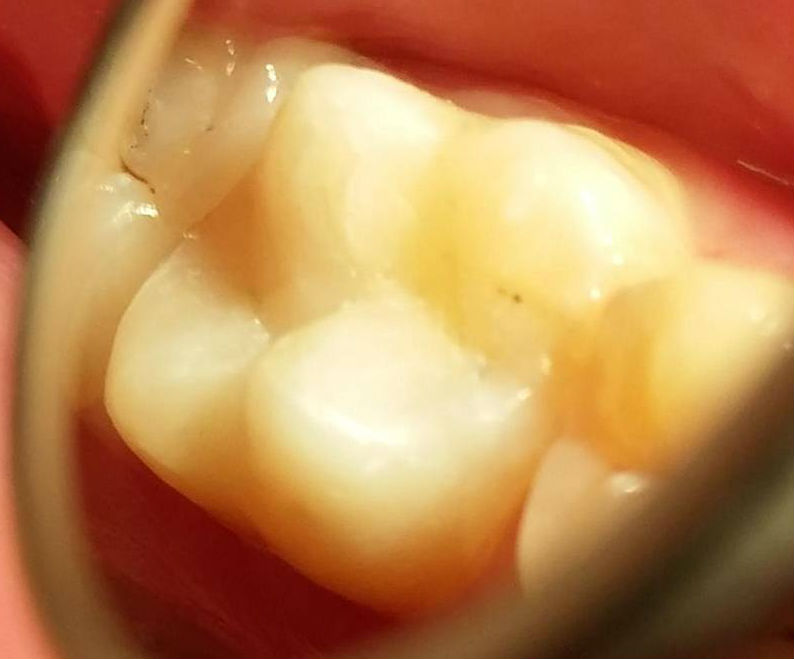

Konkurs sprawdzał umiejętności praktyczne studentów i dotyczył odbudowy zębów w odcinku przednim lub bocznym z użyciem materiałów stomatologicznych Dentsply Sirona.